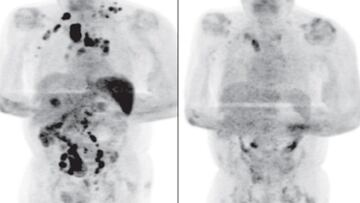

A los cuatro meses de la infección, los médicos observaron que la inflamación de los ganglios se había reducido y una exploración PET reveló una remisión generalizada del linfoma y una reducción de la captación metabólica en todas partes, explican desde la British Journal of Haemathology.